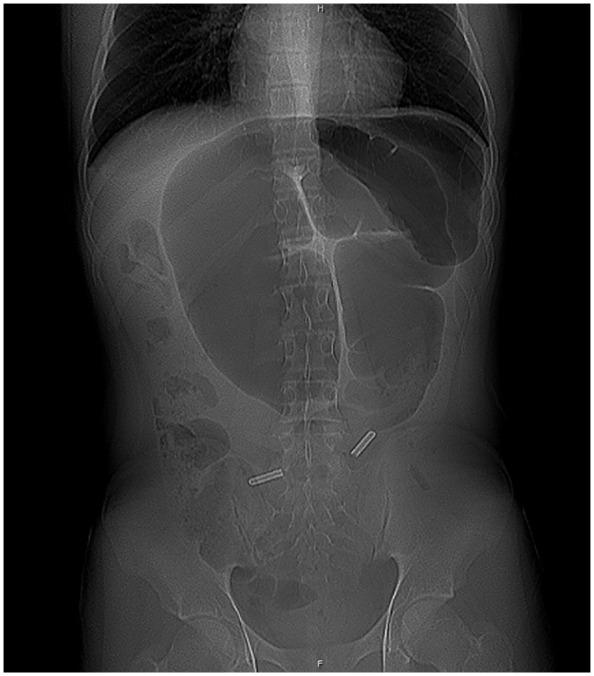

15岁男性乙状结肠扭转的内镜下复位术

Endoscopic Reduction of Sigmoid Volvulus in a 15-Year-Old Male.

Sigmoid volvulus is a well-recognized phenomenon in the elderly but rare in children. The proposed mechanism involves rotation of a redundant sigmoid loop around a narrow, elongated mesentery with subsequent vascular occlusion. The condition can be intermittent or may resolve spontaneously, complicating diagnosis. Early diagnosis is imperative to prevent ischemic complications including necrosis, perforation, and sepsis. Abdominal pain, abdominal distention, and vomiting are the most common presenting symptoms, however abdominal tenderness is uncommon. Colonic dilation is the most frequent finding on abdominal radiograph. Contrast enema reveals a "bird's beak" configuration of the twisted colon and moreover, is successful in reducing the majority of pediatric cases. If there is no evidence of bowel ischemia or perforation, endoscopic reduction has been proposed as first-line treatment for sigmoid volvulus, especially in children. We report the case of 15-year-old male in which endoscopic reduction of sigmoid volvulus was successful without complication.

摘要

乙状结肠扭转在老年人中是一种广为人知的现象,但在儿童中罕见。其推测机制包括一个冗长的乙状结肠袢围绕狭窄、细长的肠系膜旋转,随后发生血管闭塞。这种情况可以是间歇性的,也可能自行缓解,这使得诊断变得复杂。早期诊断对于预防包括坏死、穿孔和败血症在内的缺血性并发症至关重要。腹痛、腹胀和呕吐是最常见的症状表现,然而腹部压痛并不常见。结肠扩张是腹部X线片上最常见的表现。钡剂灌肠显示扭转结肠呈“鸟嘴”状,而且,大多数儿科病例通过钡剂灌肠复位成功。如果没有肠缺血或穿孔的证据,内镜复位已被提议作为乙状结肠扭转的一线治疗方法,尤其是在儿童中。我们报告了一例15岁男性患者,其乙状结肠扭转经内镜复位成功且无并发症。